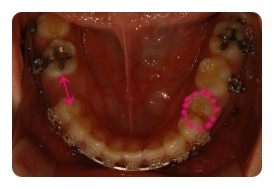

( 하악비교 )

▲ 발치전 - 왼쪽결손치, 오른쪽유치 1차삭제 예정

▲ 5월 - 스크류식립 후 본격적으로 하악당기기 1개월차

▲ 7월 - 3개월차, 오른쪽유치 2차삭제

▲ 10월 - 6개월차

물론 사진크기나 각도가 100% 일치하진않지만 최대한 비슷하게 비교해보려고 노력햇는데

어떤가요 ??

왼쪽 결손치는 발치한지 몇년되엇기때문에 이미 잇몸뼈가 굳어져서 진행이 더딜수밖에 없다고해요

그동안 꿈쩍도 안하고잇는줄 알앗는데 비교해보니 이정도면 뭐 기특하네요 ㅋㅋ

그에비해 오른쪽 유치는 조금씩 삭제하면서 당기고 잇는데요

쑥쑥 잘 움직여주고 잇어서 2차 삭제까지 햇는데도 벌써 또 닫혀가고 잇어요

아마도 다음에 가면 또 삭제할듯요 ;; 아 ~~~ 삭제할때의 시큰시큰한 느낌 시르다 ㅠㅠ